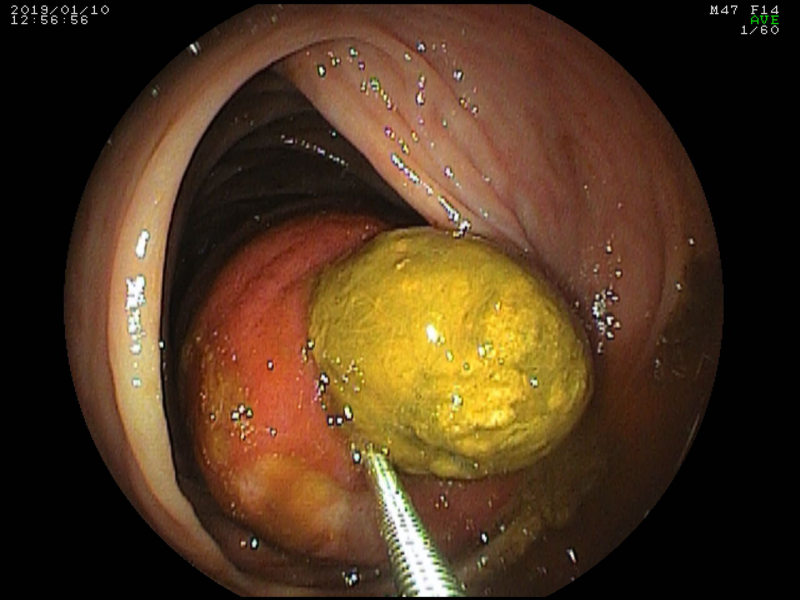

Intraductal Papillary Mucinous Neoplasm of the pancreas with gastric fistula

Fotografia